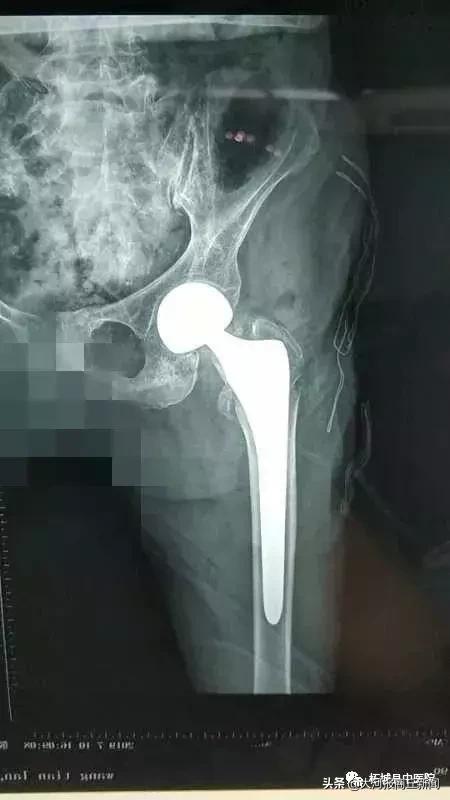

7月10日下午,在柘城县中医院北关院区百级层流净化手术室,院长殷晓东带领骨二科医师团队亲自手术,麻醉师张文选全程监控,内科专家王因仲、孙全立随时待命。仅耗时20分钟就顺利地完成了主操作。当老人被平安送出手术室的一刻,柘城县中医院乃至柘城县最高龄髋关节置换手术患者的纪录也再次被刷新。

多年来,该院院长殷晓东带领下的骨科团队在关节、脊柱、显微及关节微创临床诊断和治疗方面做了大量卓有成效的探索,尤其在骨性关节炎、股骨头坏死的诊断和治疗上积累了丰富的临床经验,率先在柘城县开展了人工髋关节置换术、人工膝关节置换术、人工肱骨头置换术等手术,新技术、新材料的应用极大提高了人工关节置换的远期疗效。

该院科室特别注重患者围手术期的无痛管理,通过多模式镇痛,髋、膝关节置换术后患者在无痛条件下做到早期活动、早期下床、早期康复;围手术期管理较早引入快速康复外科理论,使患者充分感受到无疼痛、无血栓、无感染、无管道、无呕吐等带来的优质体验、从而实现患者的快速康复,缩短住院时间,提高患者及家属满意度,真正使患者重建关节功能尽享美好人生。